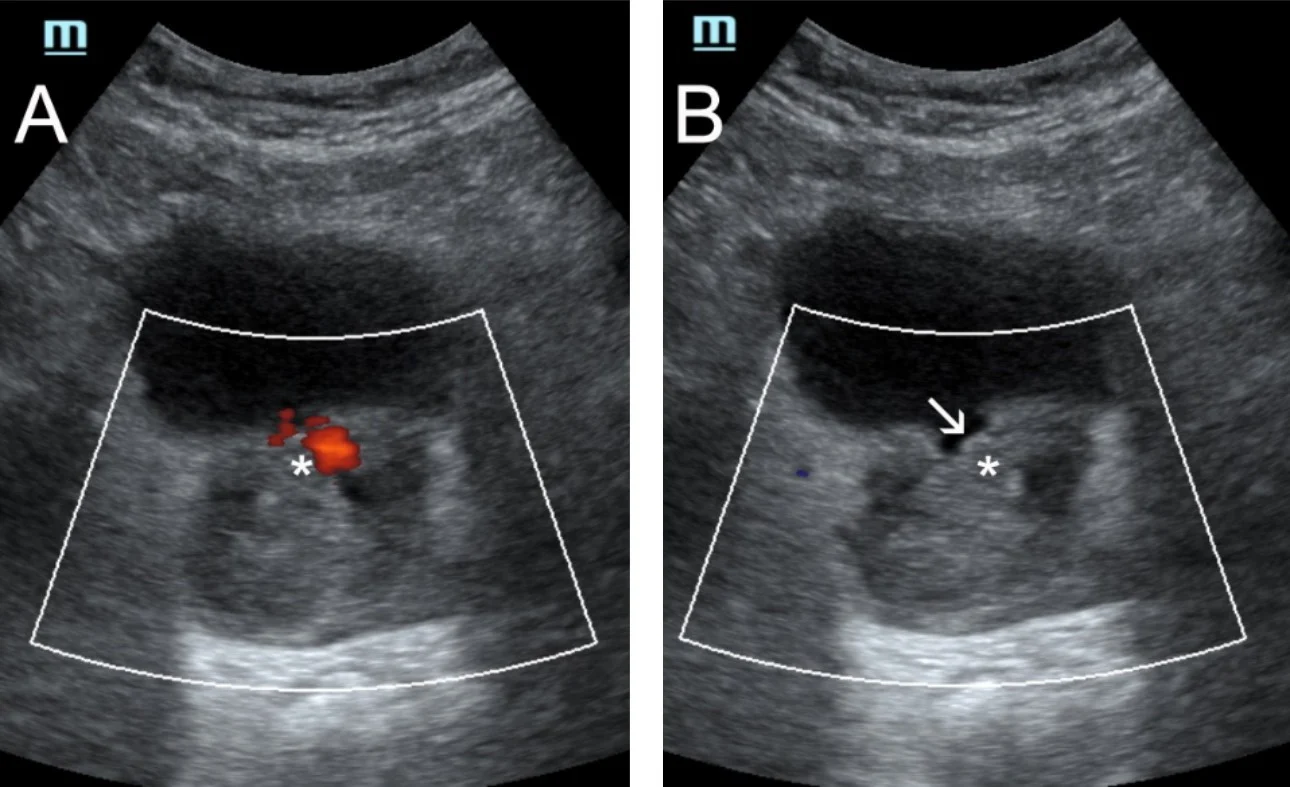

Shear-wave elastography has also been applied for the study of the prostate before and after PAE and remarkable changes in shear-wave velocity and in the elastic modulus have been recorded; US elastography can therefore detect and quantify therapeutic changes in elasticity of prostate tissue post PAE [6,7]. The respective studies have been performed with transrectal ultrasound [6,7, 8]; however initial experience at the institution of the authors indicates that, with appropriate equipment, transabdominal shear wave elastography of the prostate could also detect changes in prostate elasticity post PAE (Fig 3). This and other research purposes are served by a high-end machine (Resona I9, Mindray) with a wide variety of probes.

Figure3: Τransabdominal shear-wave elastography of the prostate before (A), and 20 days post (B), successful bilateral PAE. A decrease in the elastic modulus is apparent on post embolization image. Although relevant published data have been derived from studies with transrectal probes, initial experience of the authors suggests that transabdominal shear-wave elastography could also be an option for the investigation of the potential therapeutic changes in prostate elasticity post PAE